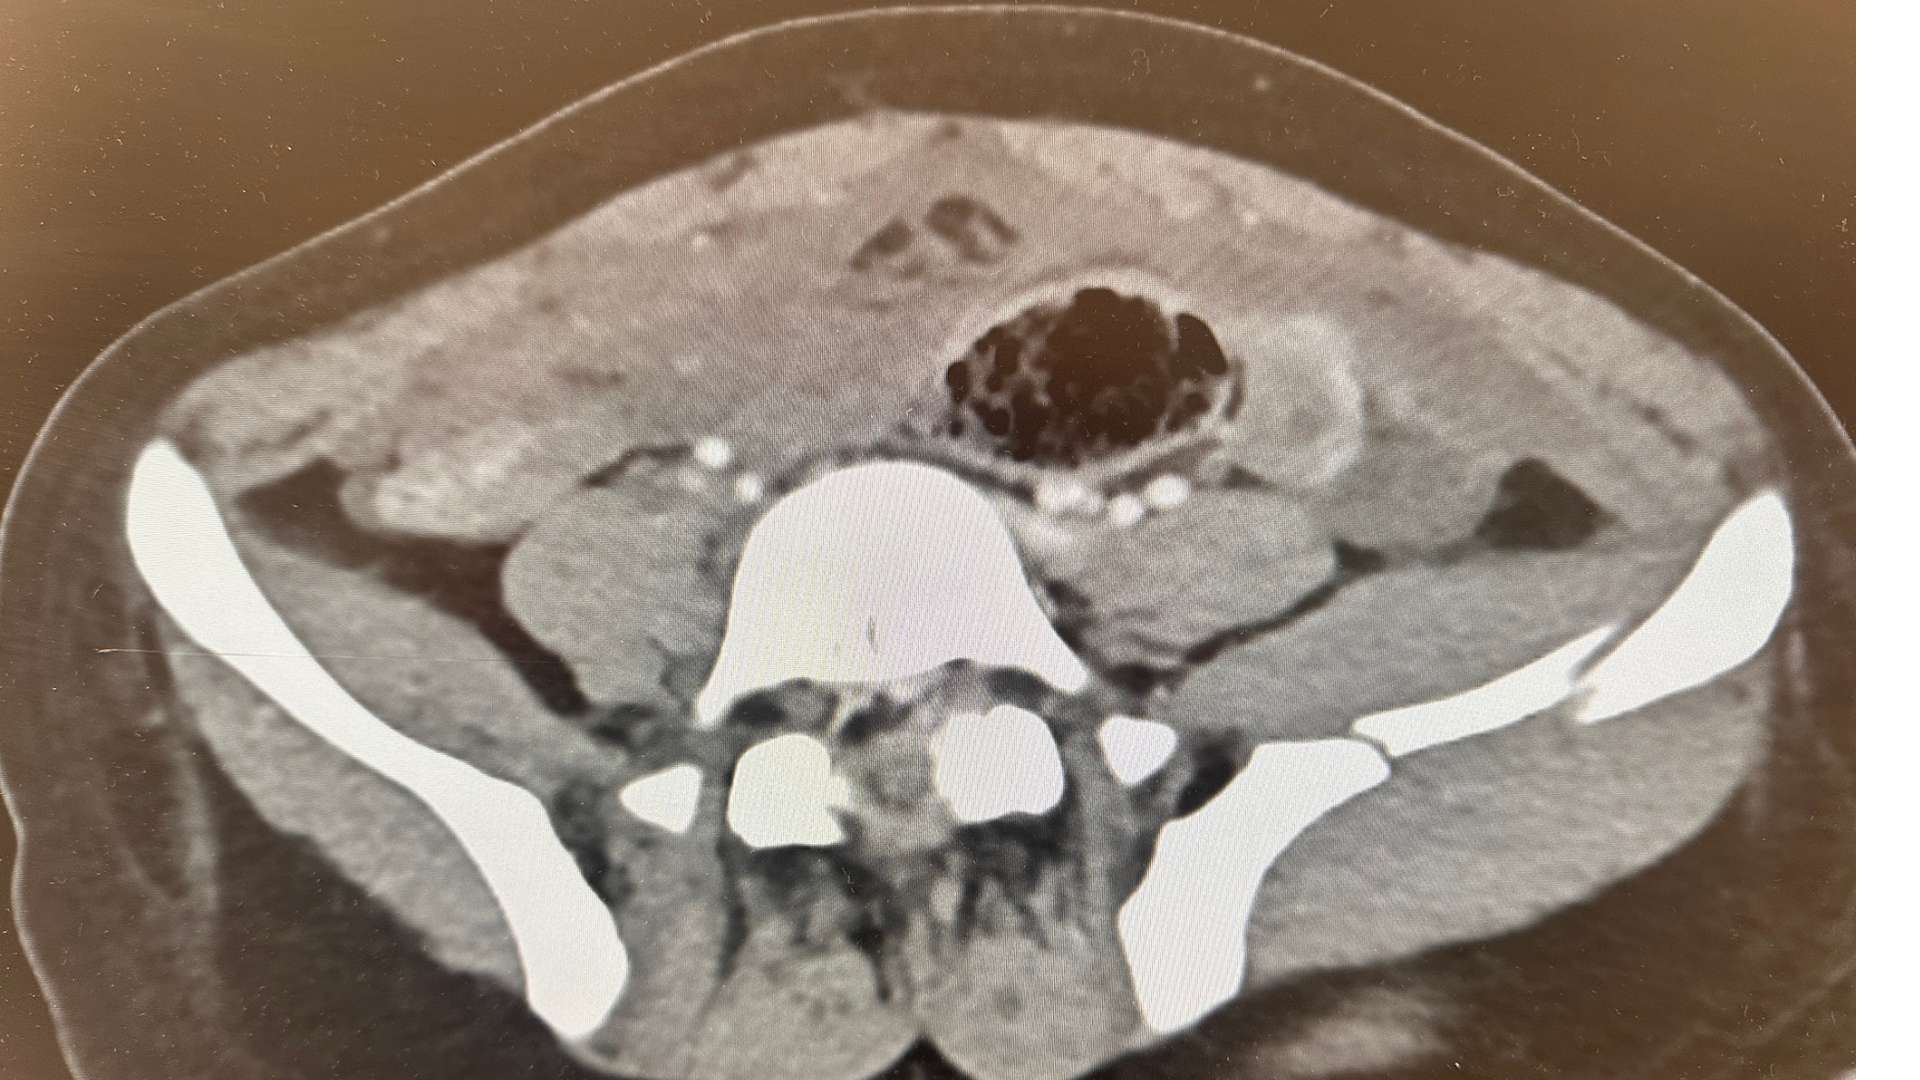

Ein zertrümmertes Becken und ein Arzt, der nicht operieren darf

Heute Morgen kam eine junge Frau ins Hospital, die sagte, sie sei aus einem fahrenden Auto geschleudert worden. Durch die Frontscheibe. Die Verletzungen passen jedoch nicht zur Beschreibung. Ihr Becken ist zertrümmert. Eine Stelle von mehreren zeigt das obige Bild.

In Deutschland würde so etwas operiert werden. In Peru wird ihr möglicherweise niemand helfen. Wir wissen, wenn wir sie verlegen, liegt sie mindestens zwei Wochen ohne OP in einem Krankenhaus mit schlechter Hygiene. Wenn sie operiert wird, ist die OP so kompliziert, dass sie daran verbluten kann. Ganz zu schweigen von der Infektionsgefahr.

Das Bitterste dabei ist, dass wir einen Facharzt bei uns haben, der in der Schweiz jahrelang unfallchirurgisch operiert hat. In Peru wird seine Lizenz bisher nicht anerkannt. Er darf diese Frau nicht operieren. Also behalten wir sie, stabilisieren sie, und hoffen das Beste.